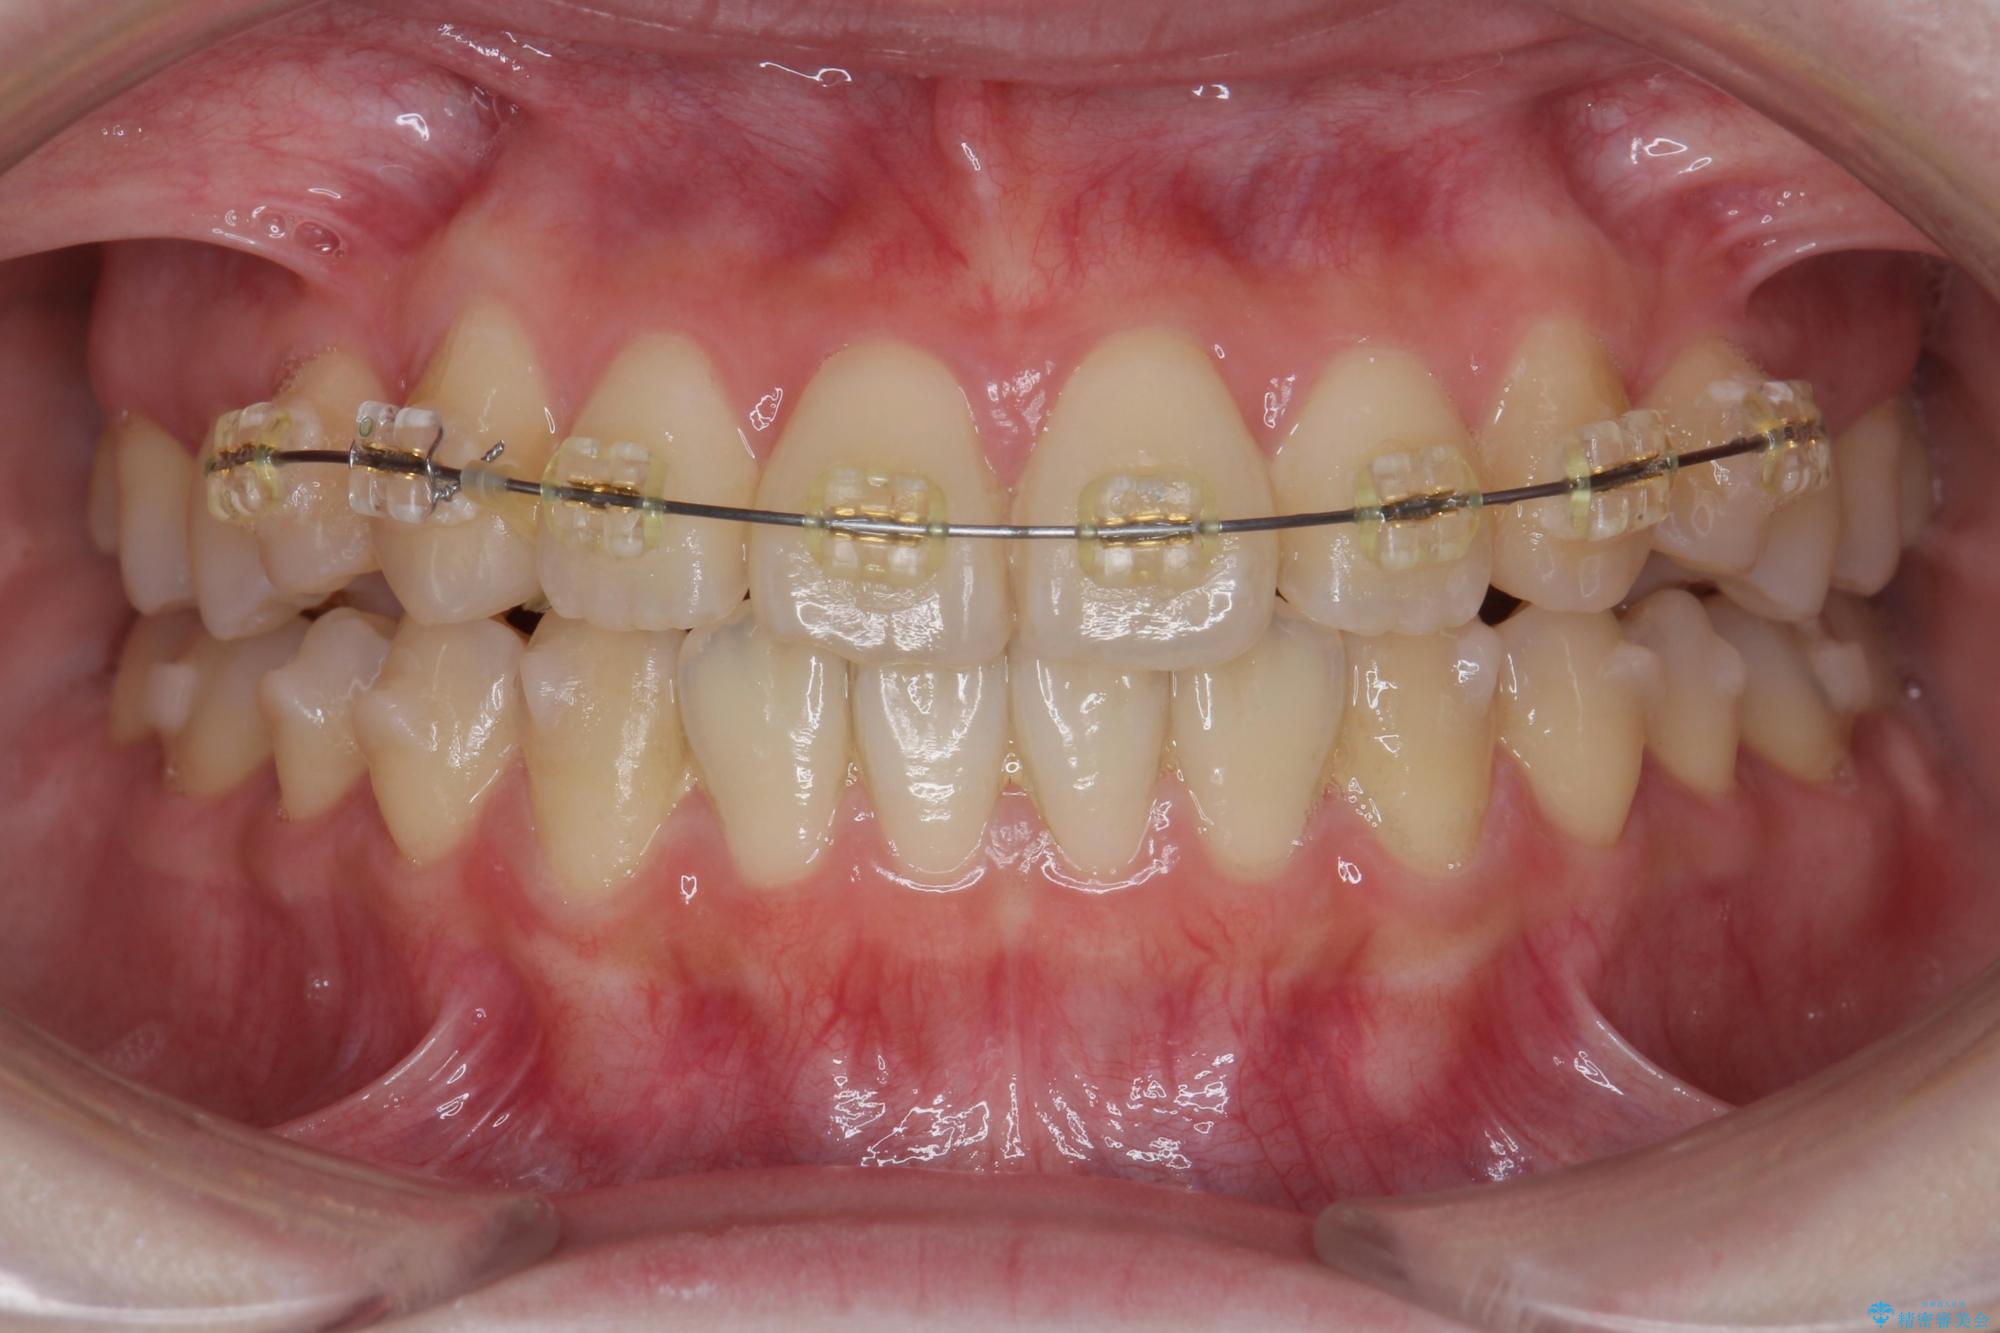

インビザライン +部分ワイヤー矯正

歯のねじれをきれいに取るのは、インビザライン(マウスピース矯正)だけでは難しい動きです。そのため、事前に4か月間の部分ワイヤー矯正を行い、治療期間を短くし、より美しい仕上がりを目指す計画です。